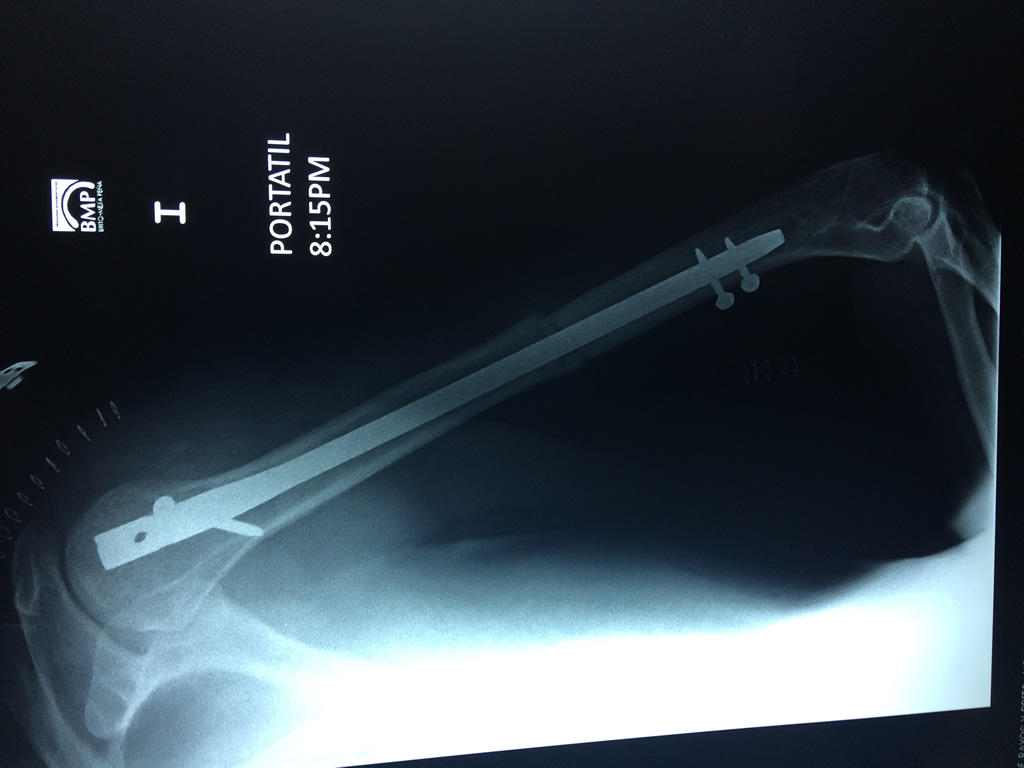

Cirugías de Húmero - Húmero

El Húmero (en latín, humerus) es el hueso más largo de las extremidades superiores en el ser humano. Forma parte del esqueleto apendicular superior y está ubicado en la región del brazo. ... El extremo proximal del húmero tiene la cabeza, cuellos quirúrgico y anatómico y tubérculos mayor y menor.